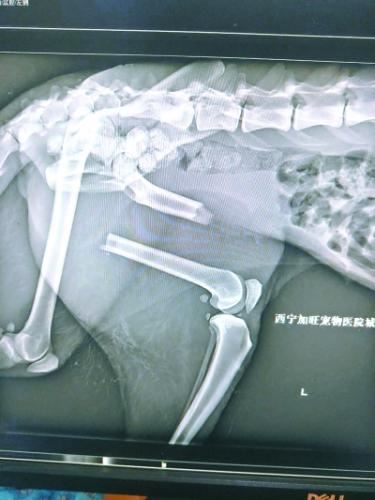

“凌雪”左后腿受伤严重

今年1月23日,饲养员发现“凌雪”步态异常,似乎又不能用力了。饲养员随即联系兽医,将“凌雪”麻醉后再次拉到动物医院拍片,结果令所有人大吃一惊,同时也心底一凉:“凌雪”左后肢股骨的加固钢钉折断了3根,钢板扭曲,股骨再次移位,它的腿又断了!

第一次手术植入的钢钉折断了3根